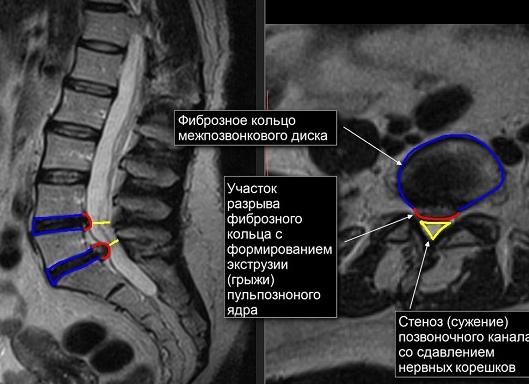

6. Выявлять опухоли, инфекции, стеноз спинномозгового канала.

• стеноз канала

9. Стеноз позвоночного канала.

12. Стеноз позвоночного канала;